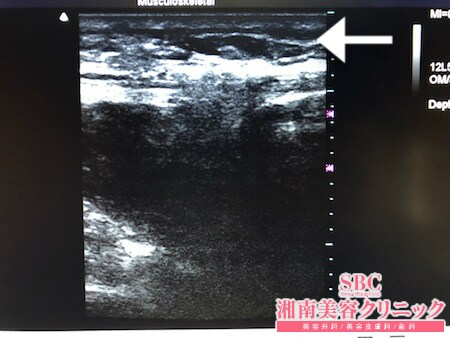

No.237872【脂肪吸引】【動画あり】湘南美容外科脂肪吸引最高責任者である竹田先生による脂肪吸引のフォトギャラリー!九州からご来院された患者様のをふくらはぎを細くする!術中3Dタッチビュー・左ふくらはぎ

画像の通りしっかりと

根こそぎ!!

脂肪吸引しておきましたので

患者様は間違いなくご満足されることでしょう。